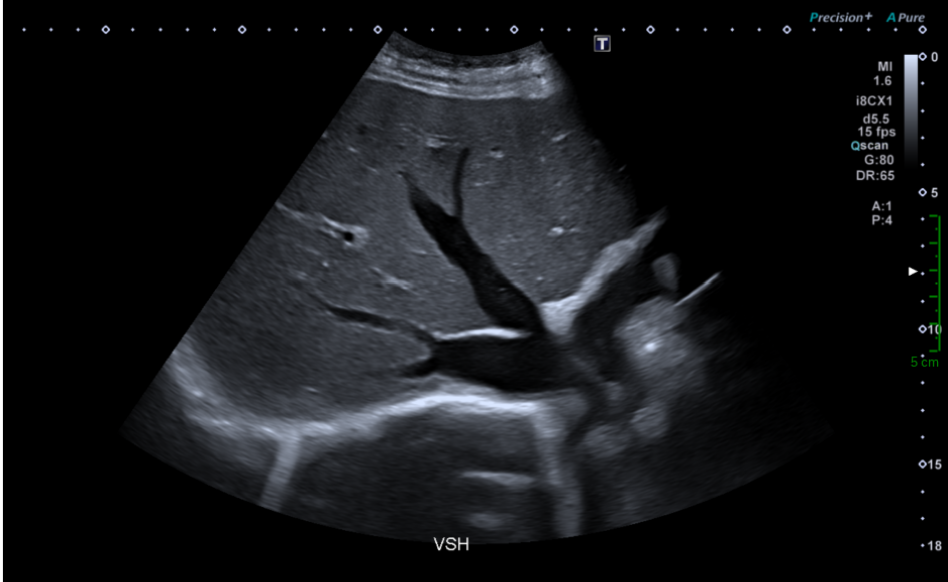

Une dilatation des veines hépatiques avec un diamètre mesuré à 16mm.

Le diamètre maximal d'une veine sus-hépatique mesuré avant son entrée dans la veine cave  inférieure est de 10 mm .

Une valeur plus élevée indique une dilatation, elle est typiquement retrouvée dans les insuffisances cardiaques droites.

Une perte du flux triphasique des veines hépatiques.

Dilatation des veines hépatiques